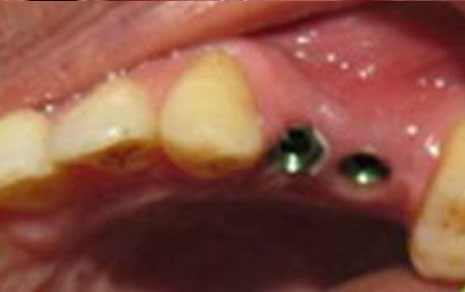

Mini Implants

Smaller implants, great for stabilizing dentures or limited bone.